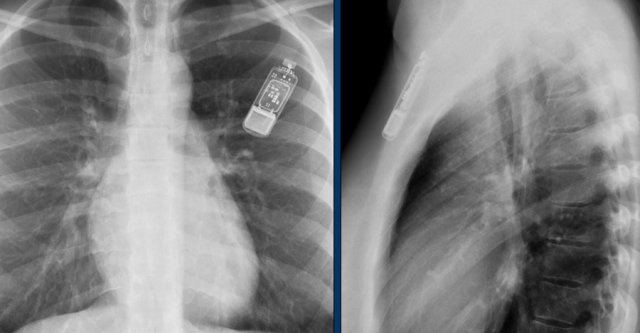

Wiireless pacemaker device

A Micra device is a small wireless pacemaker device, that is transfemorally implanted in the apex of the right ventricle.

Close up view of the Micra device.